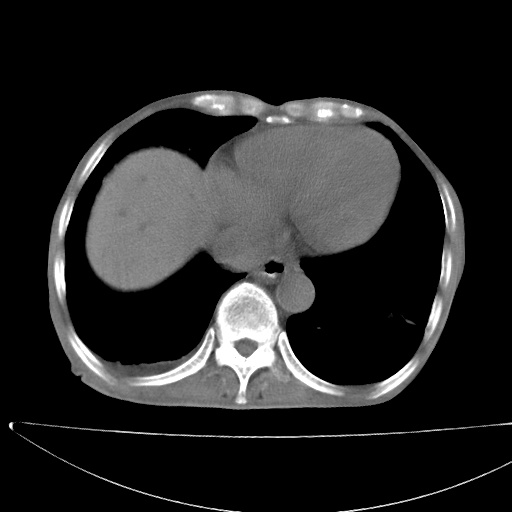

患者男70岁,上腹部不适1月。8年前有胃癌手术史。余病史不祥。

考虑胃癌复发并小网膜淋巴结转移侵及肝脏胆总管梗阻

考虑胃癌复发并腹腔内淋巴结转移。

1)胃癌术后,复发不排除。

2)肝脏转移瘤。

3)肝脏钙化灶。

4)胆囊增大。

5)腹膜后多发性淋巴结转移。

6)腹水。

7)右侧少量胸水。

建议:增强扫描。

考虑胃窦癌肝门转移

考虑胃癌复发并腹腔内淋巴结转移,胆总管受侵。

考虑胃窦癌肝门区淋巴结转移!

1)胃癌术后,不排除复发可能。2)考虑肝脏及腹膜后淋巴结转移瘤。3)肝内胆管扩张,胆囊增大。4)肝内胆管结石(或钙化)。5)脾脏钙化灶。6)腹水。7)右侧少量胸腔积液。

建议:行ct增强扫描检查。

1、胃癌根治胃空肠吻合术后,残胃癌?

2、肝门区占位性病变并胆道上段梗阻(肝内胆管扩张、胆囊增大),考虑肝门区淋巴结转移累及胆总管,建议ct增强扫描;

3、右侧胸腔少量积液、少量腹水;

4、肝右叶胆管结石。